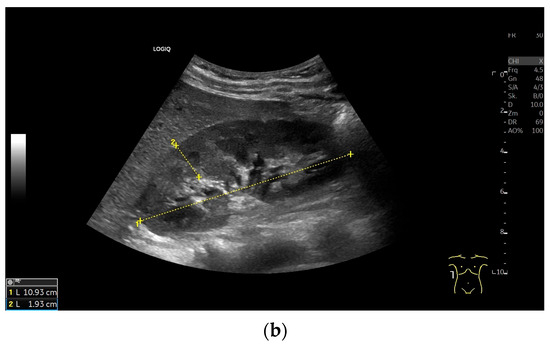

Variability of Renal Ultrasound Measurements: How Physician Experience and Patient Position Affect Measurement Accuracy?

This study was designed to investigate the variability of renal ultrasound measurements, focusing on the impact of physician experience and patient position. Background: Since decreased kidney length is considered an indicator for chronic renal disease, understanding measurement repeatability and reproducibility is crucial [...] Read more.

This study was designed to investigate the variability of renal ultrasound measurements, focusing on the impact of physician experience and patient position. Background: Since decreased kidney length is considered an indicator for chronic renal disease, understanding measurement repeatability and reproducibility is crucial for establishing effective diagnostic guidelines. Methods: Fifty healthy young adults underwent renal ultrasound scans performed by three examiners with varying levels of experience (12 years, 5 years, and 4 weeks). Renal length was measured at the level of the hilum in three patient positions: supine, lateral decubitus, and prone, using a 2–6 MHz convex probe (GE Logiq S8). Results: This study found that examiner experience significantly affected the results of sonographic measurements. However, the Interclass Correlation Coefficient analysis for all examiners demonstrated good reliability in most positions, with the highest values observed for the prone position. Measurements in the lateral decubitus position showed highest values, especially for the most experience examiner. The less experienced sonographers produced more variable results. Conclusions: Standardized patient positioning improves the accuracy and reproducibility of renal ultrasound measurements. The prone position offers a balance of reliability and practicality, especially for less experienced operators. Full article